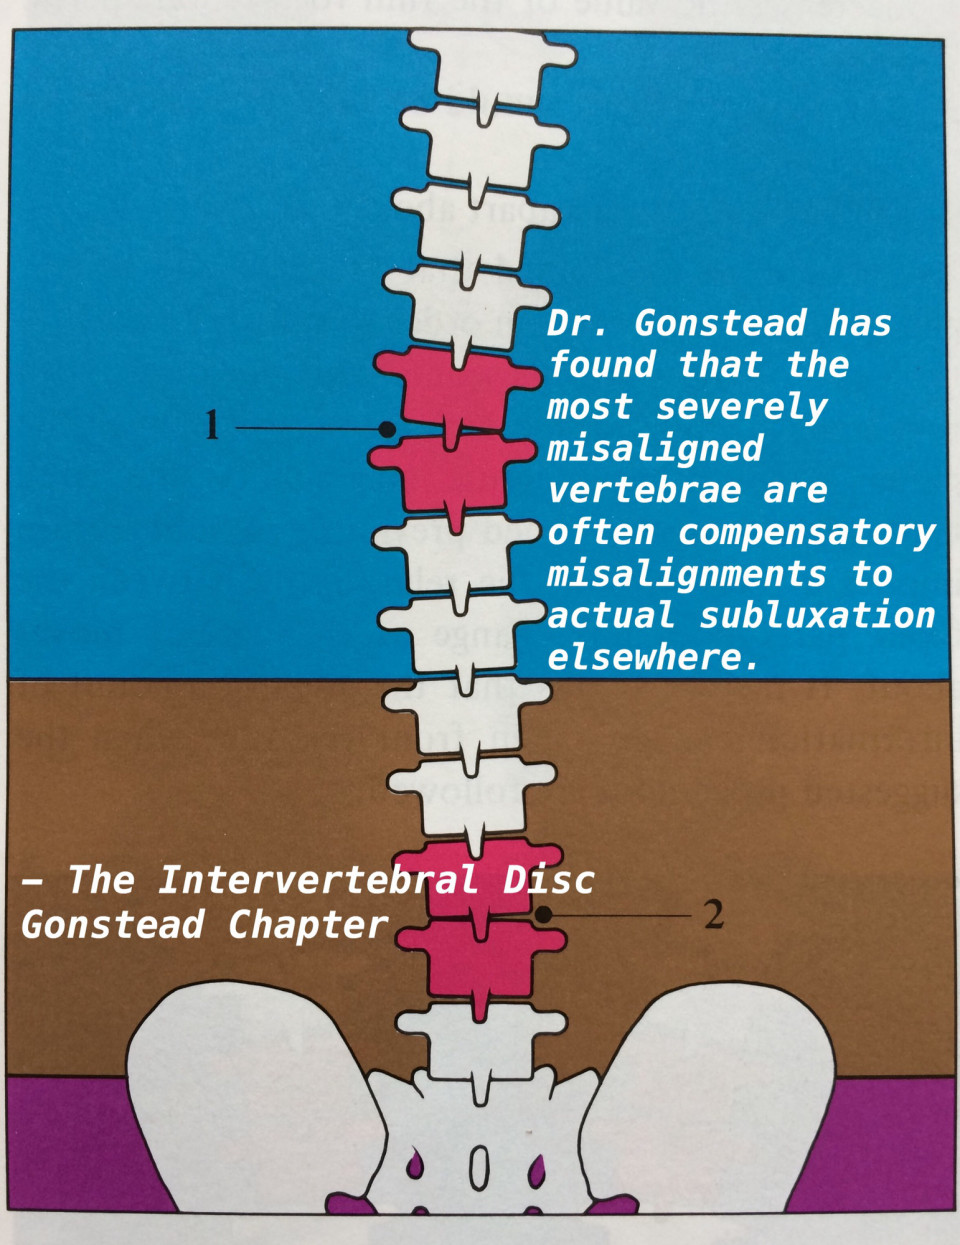

1番悪そうに見えても、そうとは限らない

1番悪そうに見えても、そうとは限らない

Compensation

Compensation